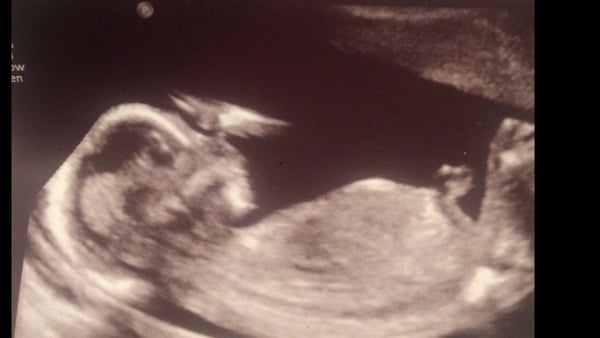

Went for my first scan today after finding out I'm further along than we originally expected. Also found out I'm having another little boy! Thrilled Grin

Thank you ladies :) I'm 17 weeks tomorrow Albus :)